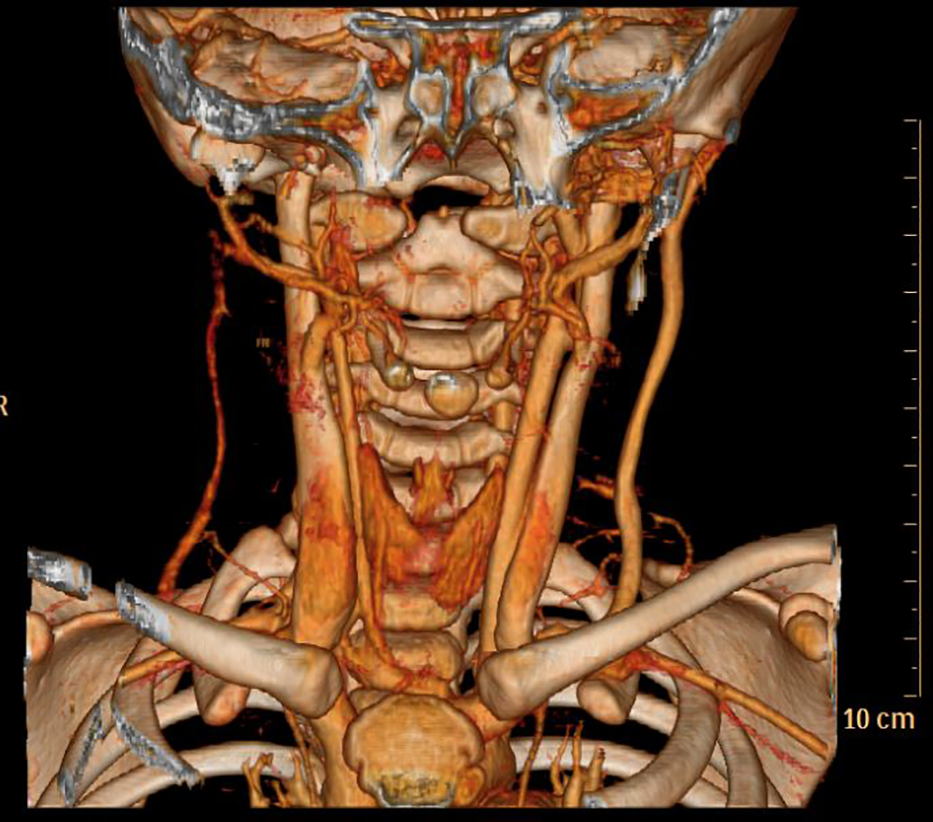

Figure 4

No. 8 patient Post-treatment 3D reconstruction,the hemangioma has disappeared.